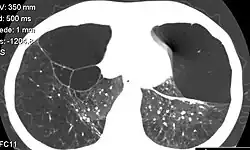

| CT scan of the lung showing bullae in the lower lung lobes of a subject with type alpha-1-antitrypsin deficiency. There is also increased lung density in areas with compression of lung tissue by the bullae. | |

A focal lung pneumatosis is an enclosed pocket of air or gas in the lung and includes blebs, bullae, pulmonary cysts, and lung cavities. Blebs and bullae can be classified by their wall thickness.[1]

- A bulla has a wall thickness of less than 1 mm.[2] By radiology definition, it has a total size of greater than 1 cm.[3] By pathology definition, it originates in the lung parenchyma (rather than in the pleurae).[4]